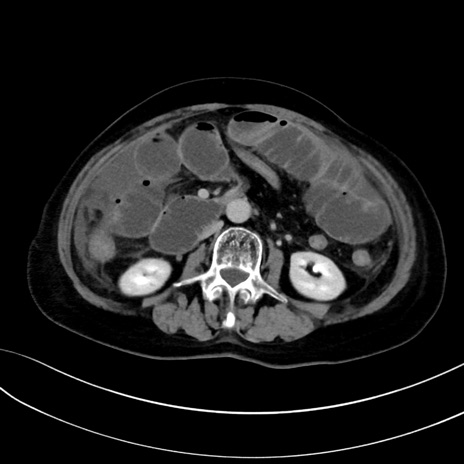

症例13 CT(横断像)1日半後